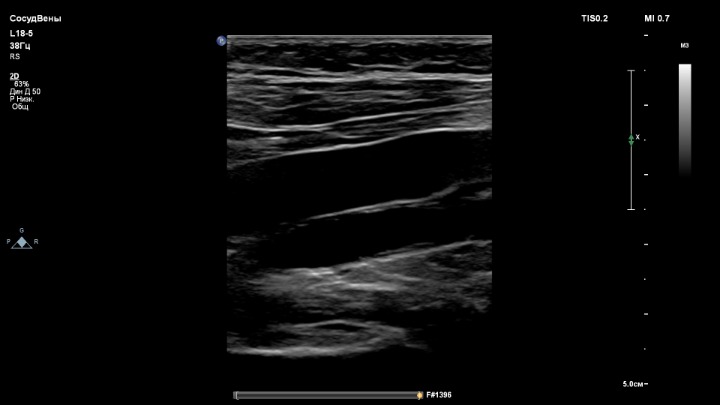

3. Датчик L18-5

- вены для датчика L18-5.

Глубина сканирования одинаковая, 5 см.

Ну если аппарат не поддерживает датчик eL18-4, тогда нужен комплект L12-3 + L18-5.

Когда работаю на аппарате с одной линейкой eL18-4, то доволен и картинкой вен нижних конечностей.